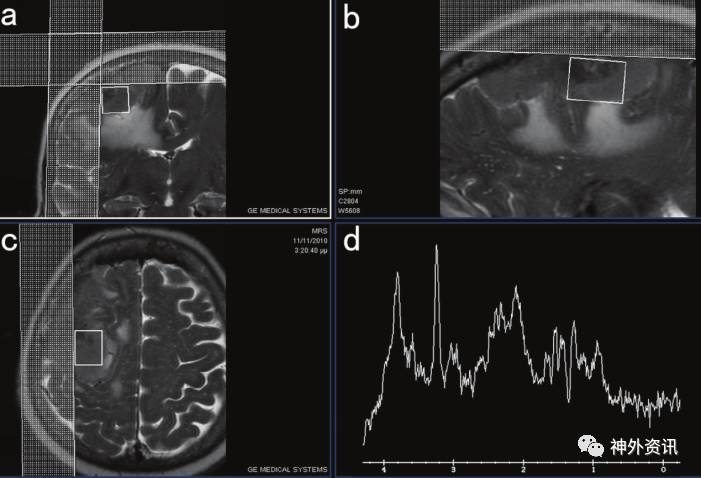

1例66岁女性患者,以“脑肿瘤”收入院治疗。患者既往有癫痫发作史,曾患与非霍奇金淋巴瘤相关的抗磷脂综合征。头颅MRI显示右额顶叶矢状窦旁增强病灶,伴明显的瘤周脑水肿,考虑为高级别胶质瘤。氢质子磁共振波谱(1H-MRS)检查发现肿瘤中心代谢为:Chol/NAA比值高,怀疑病变为胶质瘤(图1、2)。

图1. a.MRI冠状位;b.MRI矢状位;c.MRI轴位;d.在a、b、c显示的肿瘤区域中选取的体素MRS。